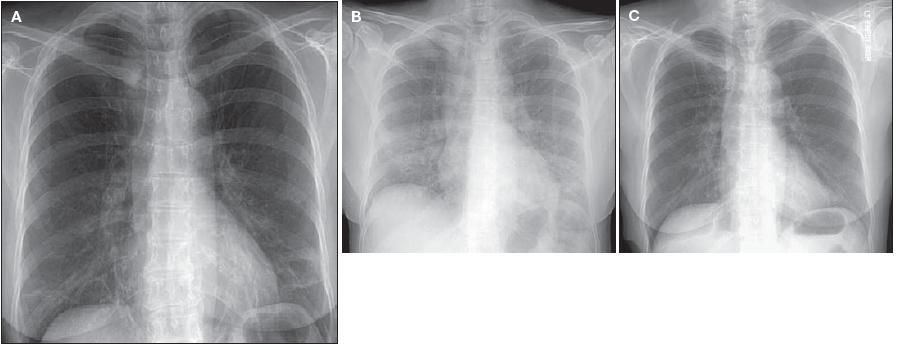

A chest radiograph obtained 2 weeks before presentation showed mild increased interstitial markings and hyperinflation (Figure 1A). A chest radiograph obtained on presentation showed new bilateral pulmonary infiltrates (Figure 1B). A CT scan of the chest showed diffuse bilateral ground-glass infiltrates (Figure 2).

Figure 1 – A chest radiograph obtained 2 weeks before presentation showed a mild increase in interstitial markings and hyperinflation (A). On presentation, the chest radiograph showed new bilateral pulmonary infiltrates (B). Treatment with prednisone resulted in resolution of the pulmonary infiltrates (C).

The patient was given oral prednisone, 40 mg daily. After 4 weeks of prednisone therapy, she reported marked improvement in diarrhea and dyspnea. A chest radiograph was repeated, and it showed resolution of the pulmonary infiltrates (Figure 1C). Marked improvement in pulmonary function test results was also noted.